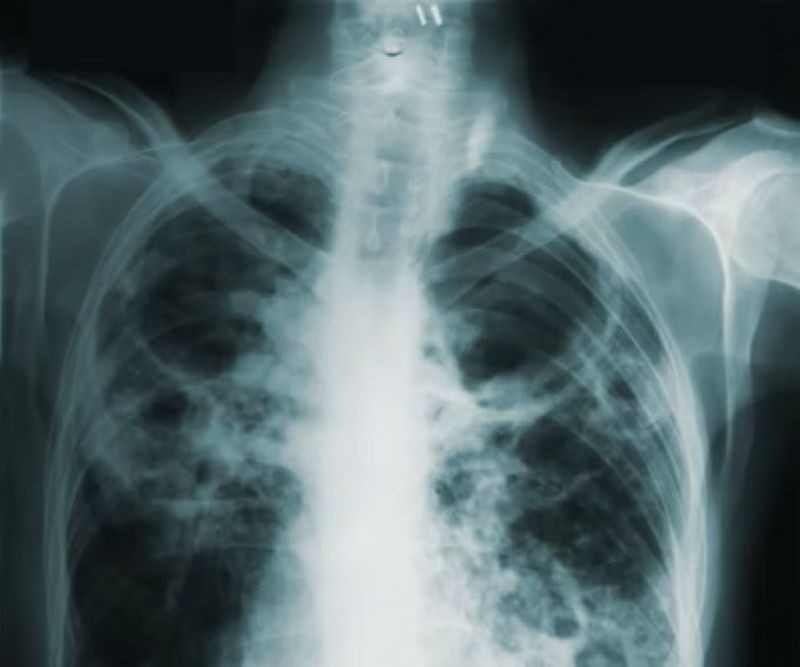

Tuberculosis

Tuberculosis (TB) remains one of the world’s deadliest infectious killers, claiming over 1.2 million lives and affecting an estimated 10.7 million people last year, according to the WHO Global Tuberculosis Report 2025, released recently.